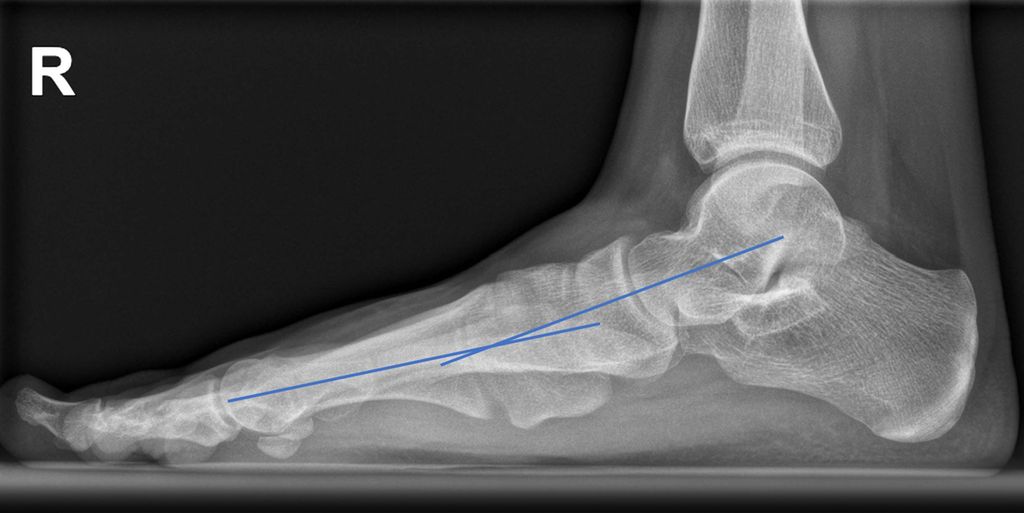

Auf der seitlichen Aufnahme sind die Abflachung des Längsgewölbes und die Lokalisation der gegebenenfalls vorliegenden Instabilität der medialen Säule zu erkennen (Talus-Metatarsale1-Winkel = „Meary’s angle“ 0°). Auch ein Metatarsus primus elevatus als Hinweis auf eine Supination des Vorfußes kann vorliegen (Abb. 2).

Abb. 2: Fuß seitlich, stehend: Talus-MT1-Winkel („Meary’s angle“), „Plantar Gapping“ bei TMT1-Instabilität